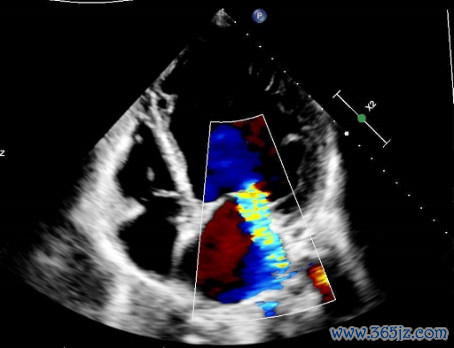

超声心动图:

左心大,左房前后径44mm,左室前后径71mm,右心各房室腔、主动脉及肺动脉内径简单;

心室壁及室远离厚度简单,各节段指令幅度减低,左室侧壁、后壁中段及心尖段肌小梁加多、呈珊瑚状改动,纰缪与室腔重迭,肌层变薄;

二尖瓣中-多量返流,三尖瓣一丝返流,主动脉瓣一丝返流,心功能减低,左心室射血分数(LVEF)30%(图2-5)。

图2 超声心动图效劳

图3 超声心动图效劳

图4 超声心动图效劳

图5 超声心动图效劳